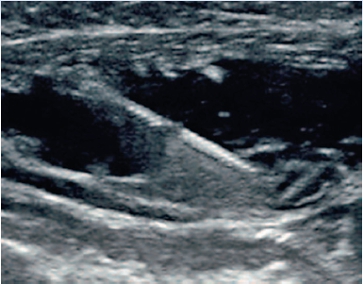

Canulele vizibile echografic cu sistem tip „cornerstone” care maximizează gradul de reflexie, permit vizibilitatea canulei în orice poziţionare.

Sistemul presupune: canulă echovizibilă, cateter perforat pentru administrarea anestezicului, adaptor, filtru, sistem de fixare.